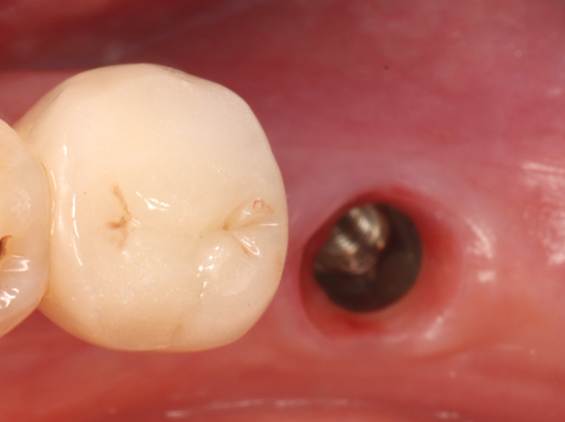

4. Wound status of Tooth #47 prior to the second-stage implant surgery (5 months post-implantation)

Completion of second-stage restoration: Healing abutment placement